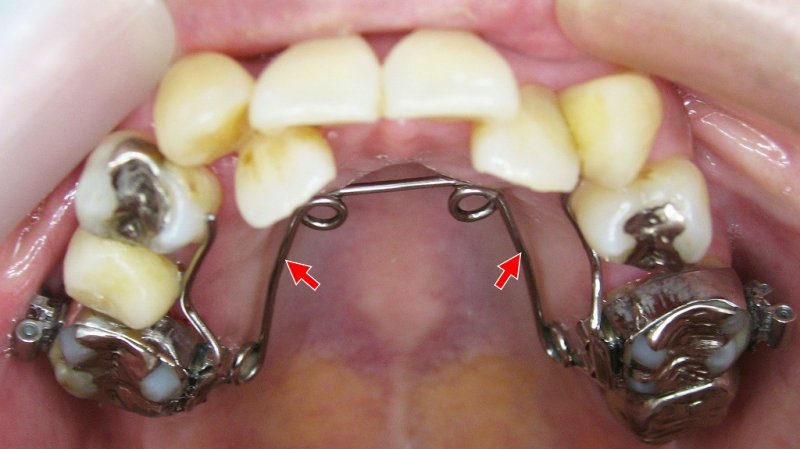

現代の子供たちは顎の成長が十分でなく、歯並びが悪くなることが多いです。当院では、「プレオルソ」というマウスピース型の装置を使った矯正治療を行っています。この装置は日中1時間と就寝時のみの装着で、口周りの筋肉を整え、歯並びを改善します。